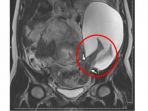

Panduan dalam pendidikan spesialisasi Obgyn di Indonesia menyarankan operasi caesar maksimal tiga kali.

Risiko pecah ketuban dapat meningkat seiring meningkatnya operasi Caesar yang dilakukan selama beberapa kali.